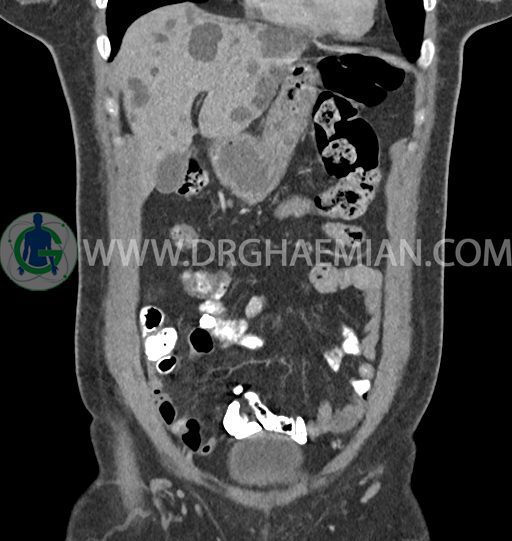

سی تی اسکن شکم و لگن با استفاده از اشعات ایکس تصاویر عرضی از ناحیه شکم و لگن ایجاد میکند. در این کیس کبد پلی کیستیک، کیست در تخمدان چپ، توده در دیواره سرویکس و اسپوندیلولایزیس دو طرفه مهره L5 دیده می شود.

در سی تی اسکن اسپیرال شکم و لگن – 5Phasic (بدون کنتراست – با کنتراست در فاز آرتریال ، پورتال و تاخیری 5 دقیقه و 10 دقیقه، مولتی دیدکتور 16 با مقاطع ظریف و بازسازی های ساژیتال و کرونال) :

-ضایعات سیستیک فراوان به قطر 5 تا 30mm پراکنده در کبد بدون جزء سالید، بدون septation و بدون اینهنسمنت پس از تزریق کنتراست مطرح کننده polycystic liver disease

-کیست ساده به قطر 31mm در تخمدان چپ

-توده هیپودنس به قطر 13mm در دیواره قدامی سرویکس نیازمند مطابقت سونولوژیک

-اسپوندیلولایزیس دو طرفه L5 همراه با آنترولیستزیس gread 1 و تغییرات DJD در L5/S1

مشهود است.